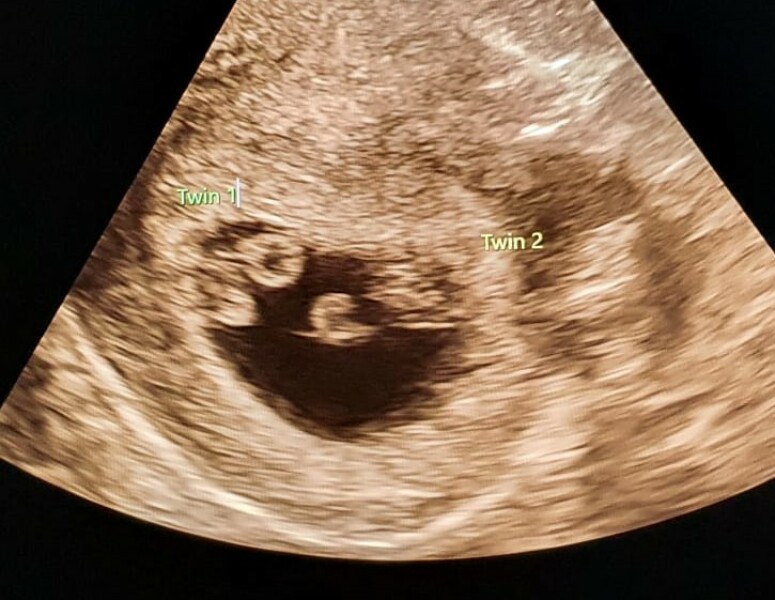

Rose993 · 14/06/2024 13:51

Hiya

I had an ultrasound at 6 weeks at my EPU because of cramping and spotting & suspected ectopic. Scan pic attached, the ultrasound only lasted a few minutes the tech pointed out baby and it’s heartbeat then checked ovaries too and that was that. I got this pic and I’m pretty sure I can see a second baby/ ‘diamond ring’ which they say they look for early on, up at the top.

Anyone else see it and if you’ve had identical twins had a similar early scan? Am I just imagining it? Could it be a shadow?

I have another scan next week so will update!